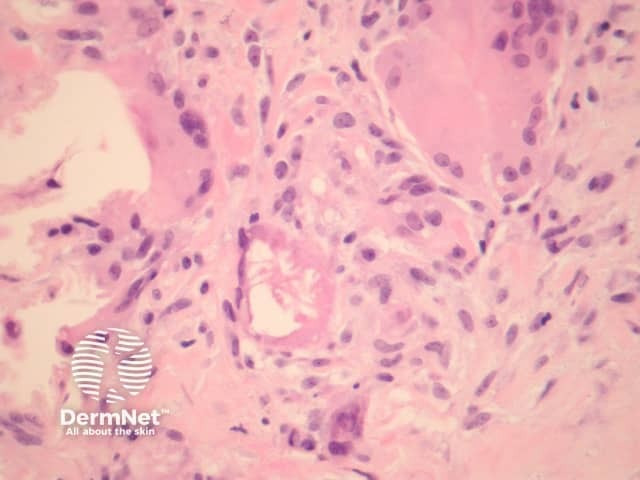

Erythema nodosum histologically represents the prototype of a septal panniculitis. The classic histopathologic presentation of erythema nodosum is that of a septal panniculitis with a mixed cellular infiltrate of lymphocytes, histiocytes, giant cells, and occasional eosinophils and a characteristic absence of vasculitis (figures 1-3).

Miescher's radial granulomata that consist of small nodules composed of spindle to oval-shaped histiocytes arranged around minute slits are thought to be a relatively specific finding for erythema nodosum (figure 4).

Early lesions may be difficult to diagnose on histopathologic features alone. Sections may show oedematous septa containing a prominent mixed inflammatory infiltrate, and minimal fibrosis. As the lesions evolve, there is neutrophilic infiltration followed by chronic infiltrates, granulomas and septal fibrosis.

Small vessel vasculitis (or venulitis) may be seen in early lesions.